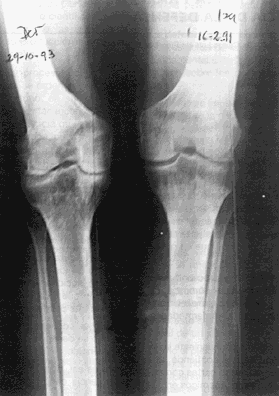

8 de diciembre de 1992 Rodilla izquierda en eje, mientras la rodilla derecha continúa valga

La osteotomía de la rodilla derecha, se realiza siguiendo las mismas indicaciones pre y postquirúrgicas a las que fue sometida la rodilla izquierda y se lleva a cabo dos años después el 29 de octubre de 1993.

Control realizado el 8 de julio del 2001 Osteotomías consolidadas y alineadas. Marcha normal